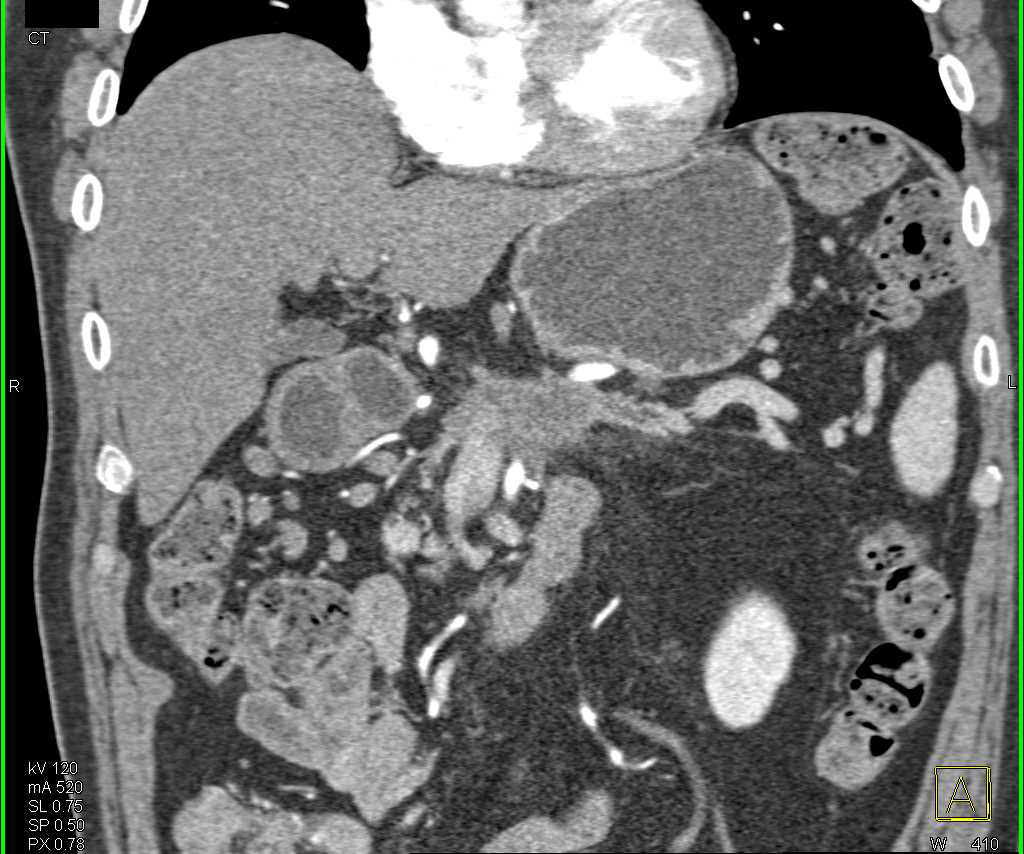

Les auteurs ont utilisé un registre national recensant les cas de KP opérables entre 2006 et 2015, en éliminant les porteurs de métastases ; ils ont trouvé 16 597 dossiers avec une classification TN précise ; ils ont été classés de T1(tumeur limitée au pancréas) à T3 (tumeur étendue aux organes voisins) et de N0 (pas d’adénopathies) à N1 (envahissement des ganglions régionaux). En cas de chirurgie première, la concordance entre les données cliniques et pathologiques a été souvent observée, mais il est arrivé que les secondes soient plus ou moins évoluées que l’on ne le prévoyait.

Sur les 16 597 patients, 13 982 (84 %) ont eu une chirurgie première et 16 % un TNA. Or, si la survie des stades précoces a été peu affectée par le TNA, ce dernier a permis une amélioration de la survie globale dans les stades avancés (cT3 ou cN1) qui passe de 17 mois en cas de chirurgie première à 26 mois en cas de TNA. Qui plus est, cette prolongation de survie se maintient même quand il n’y a pas eu de rétrogradation du stade.